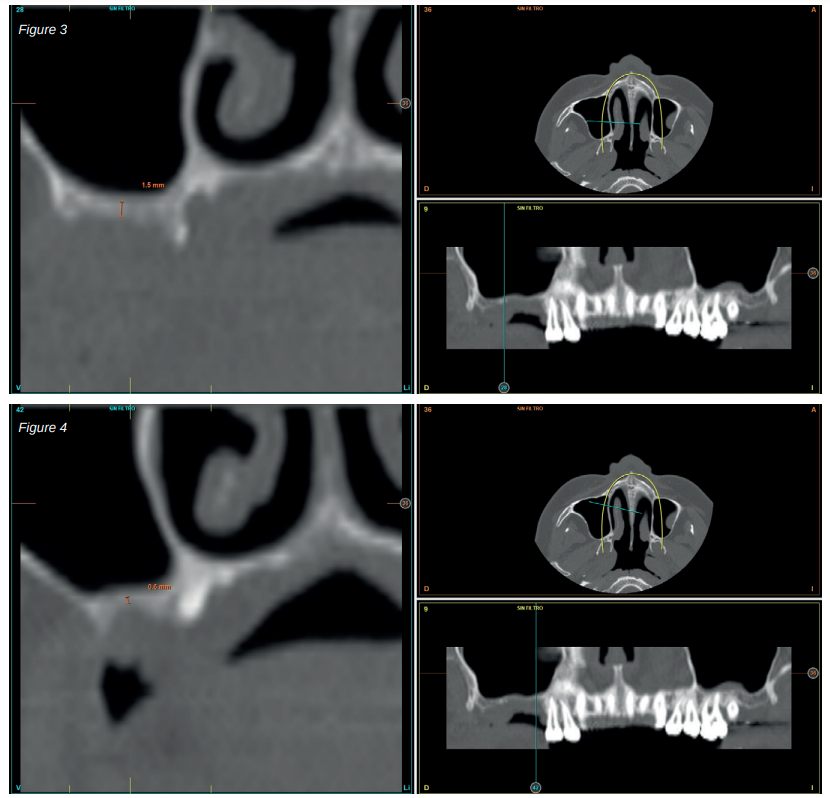

After two months, the dental cone-beam showed the perforation had closed completely but the residual bone volume provided 2 mm of bone height only, which was insufficient to insert the implants (Figures 3 and 4).